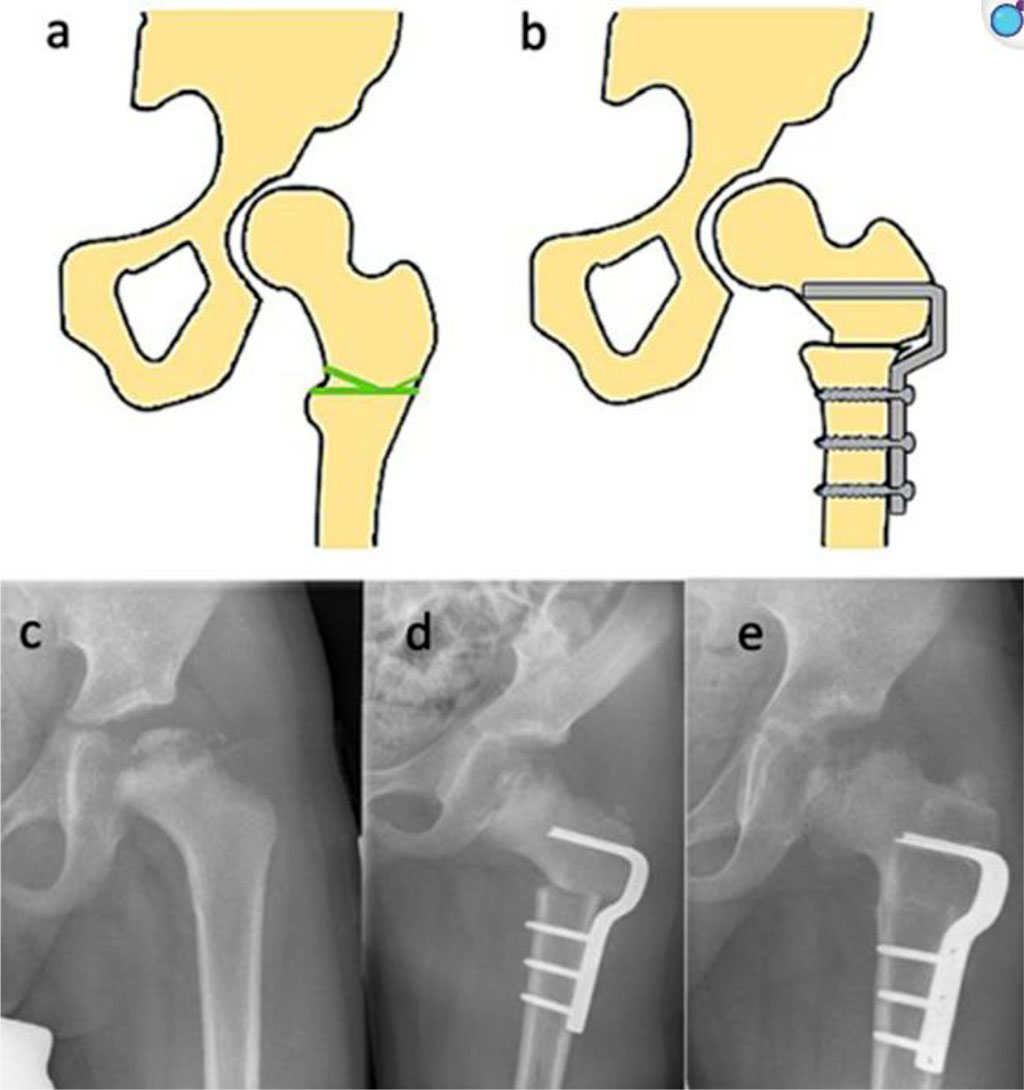

![Fig. 3 Femoral varus osteotomy (FVO) [40].](artikel-29-bild-3.jpg)

Fig. 3 Femoral varus osteotomy (FVO) [40].

One of the most commonly used surgical techniques in the treatment of LCPD is Femoral Varus Osteotomy (FVO). The goal of this procedure is to centralize the femoral head within the acetabulum, which promotes proper remodeling of its structure and can alter the natural course of the disease—particularly during the fragmentation stage—by slowing its progression to more advanced stages [41]. This technique was first described by Axer in 1963 and has since undergone numerous modifications. Today, the osteotomy is most commonly performed through an intertrochanteric approach, and advancements in stabilization techniques have allowed the replacement of traditional plates with more advanced implants featuring a predefined varus angle. The surgical method can be tailored based on the extent of necrosis affecting the femoral head. The operation offers several options for optimally positioning the femoral head within the acetabulum. Technical variations include correction in the frontal plane (varus angulation), sagittal plane (flexion-extension osteotomy), and transverse plane (derotational osteotomy), enabling precise alignment of the femoral head in the socket. These practices allow for an individualized approach based on patient anatomy. It is worth noting that this procedure is technically simpler to perform than pelvic osteotomies, which may influence the surgeon’s choice. However, FVO also has significant drawbacks. The most common complication is limb shortening on the operated side. Literature reports a typical discrepancy of approximately 1 cm, which may lead to gait disturbances. Furthermore, the surgery causes proximal displacement of the gluteus medius and minimus muscle attachments, potentially reducing muscle strength and contributing to the development of Trendelenburg gait and Duchenne’s intermittent claudication. For this reason, comprehensive postoperative physiotherapy is a crucial component of treatment. This includes the use of shoe lifts to equalize limb length, strengthening exercises for the gluteal muscle group, and maintenance of proper hip joint mobility [42, 43].

The Salter Innominate Osteotomy (SIO) involves a transverse osteotomy performed proximal to the hip joint. The distal fragment of the osteotomy is then displaced laterally and anteriorly. This maneuver is intended to improve the coverage of the femoral head by the acetabulum. In the next stage of the procedure, a bone wedge is harvested from the iliac crest and used to maintain the corrected position of the osteotomy. The final phase of the surgery involves the fixation of all bony elements to ensure optimal stabilization of the anatomical structures. Precise immobilization of the bone fragments is crucial to create proper conditions for bone union and tissue regeneration. The most commonly used tools for fixation are Kirschner wires. However, their use may be associated with complications such as migration of the wires beyond the drill channel or into the pelvic cavity. This poses a risk to surrounding structures and often necessitates surgical removal of the wires. Additionally, if displacement occurs shortly after the procedure, it may lead to pelvic instability, which significantly increases the risk of serious complications. An interesting alternative to traditional fixation methods is the use of resorbable screws. Their primary advantage is that implant removal is not required after the healing process is complete, eliminating the need for a second surgery. As a result, the risks associated with general anesthesia are reduced, hospital stay is shortened, and overall treatment costs are lowered. Importantly, the absence of the need to remove the implants allows the surgeon to position them more optimally. Furthermore, resorbable screws are associated with a lower risk of infection compared to Kirschner wires. Unfortunately, according to available studies, resorbable screws demonstrate lower mechanical stability than traditional wires, which can significantly affect their application in certain clinical scenarios [44, 45].

Triple Pelvic Osteotomy involves cutting all three bones that form the pelvis — the ilium, pubis, and ischium — to reorient the acetabulum of the hip joint. The osteotomies are performed as close to the joint as possible, which promotes effective healing and provides high postoperative stability. Unlike procedures performed on the femur, triple osteotomy does not disrupt the biomechanics of the hip joint. For instance, a potential undesirable consequence of a femoral varus osteotomy is weakening of the hip abductor muscles — a complication not observed with triple pelvic osteotomy. Notably, this procedure also does not result in limb shortening. However, the method has limitations. It involves a technically demanding surgical technique and carries a risk of significant blood loss [46]. In severe cases, such as advanced femoral head deformity where neither femoral nor pelvic procedures alone are likely to restore normal hip joint biomechanics, combined surgical interventions are recommended. These procedures are most commonly performed in older patients with prominent clinical symptoms and yield the best outcomes in terms of restoring the physiological function of the hip joint. Nevertheless, combining two surgical techniques also increases the risk of complications specific to each individual method, as well as those arising from their simultaneous use. Moreover, the use of two techniques prolongs the duration of surgery. Studies have shown that longer surgical times are associated with a higher risk of postoperative wound infection [47, 48].

Fig. 4 (left) Anteroposterior radiograph of a nine-year-old male with LCPD; (right) Result three months postoperatively after combined femoral and iliac osteotomy [50].